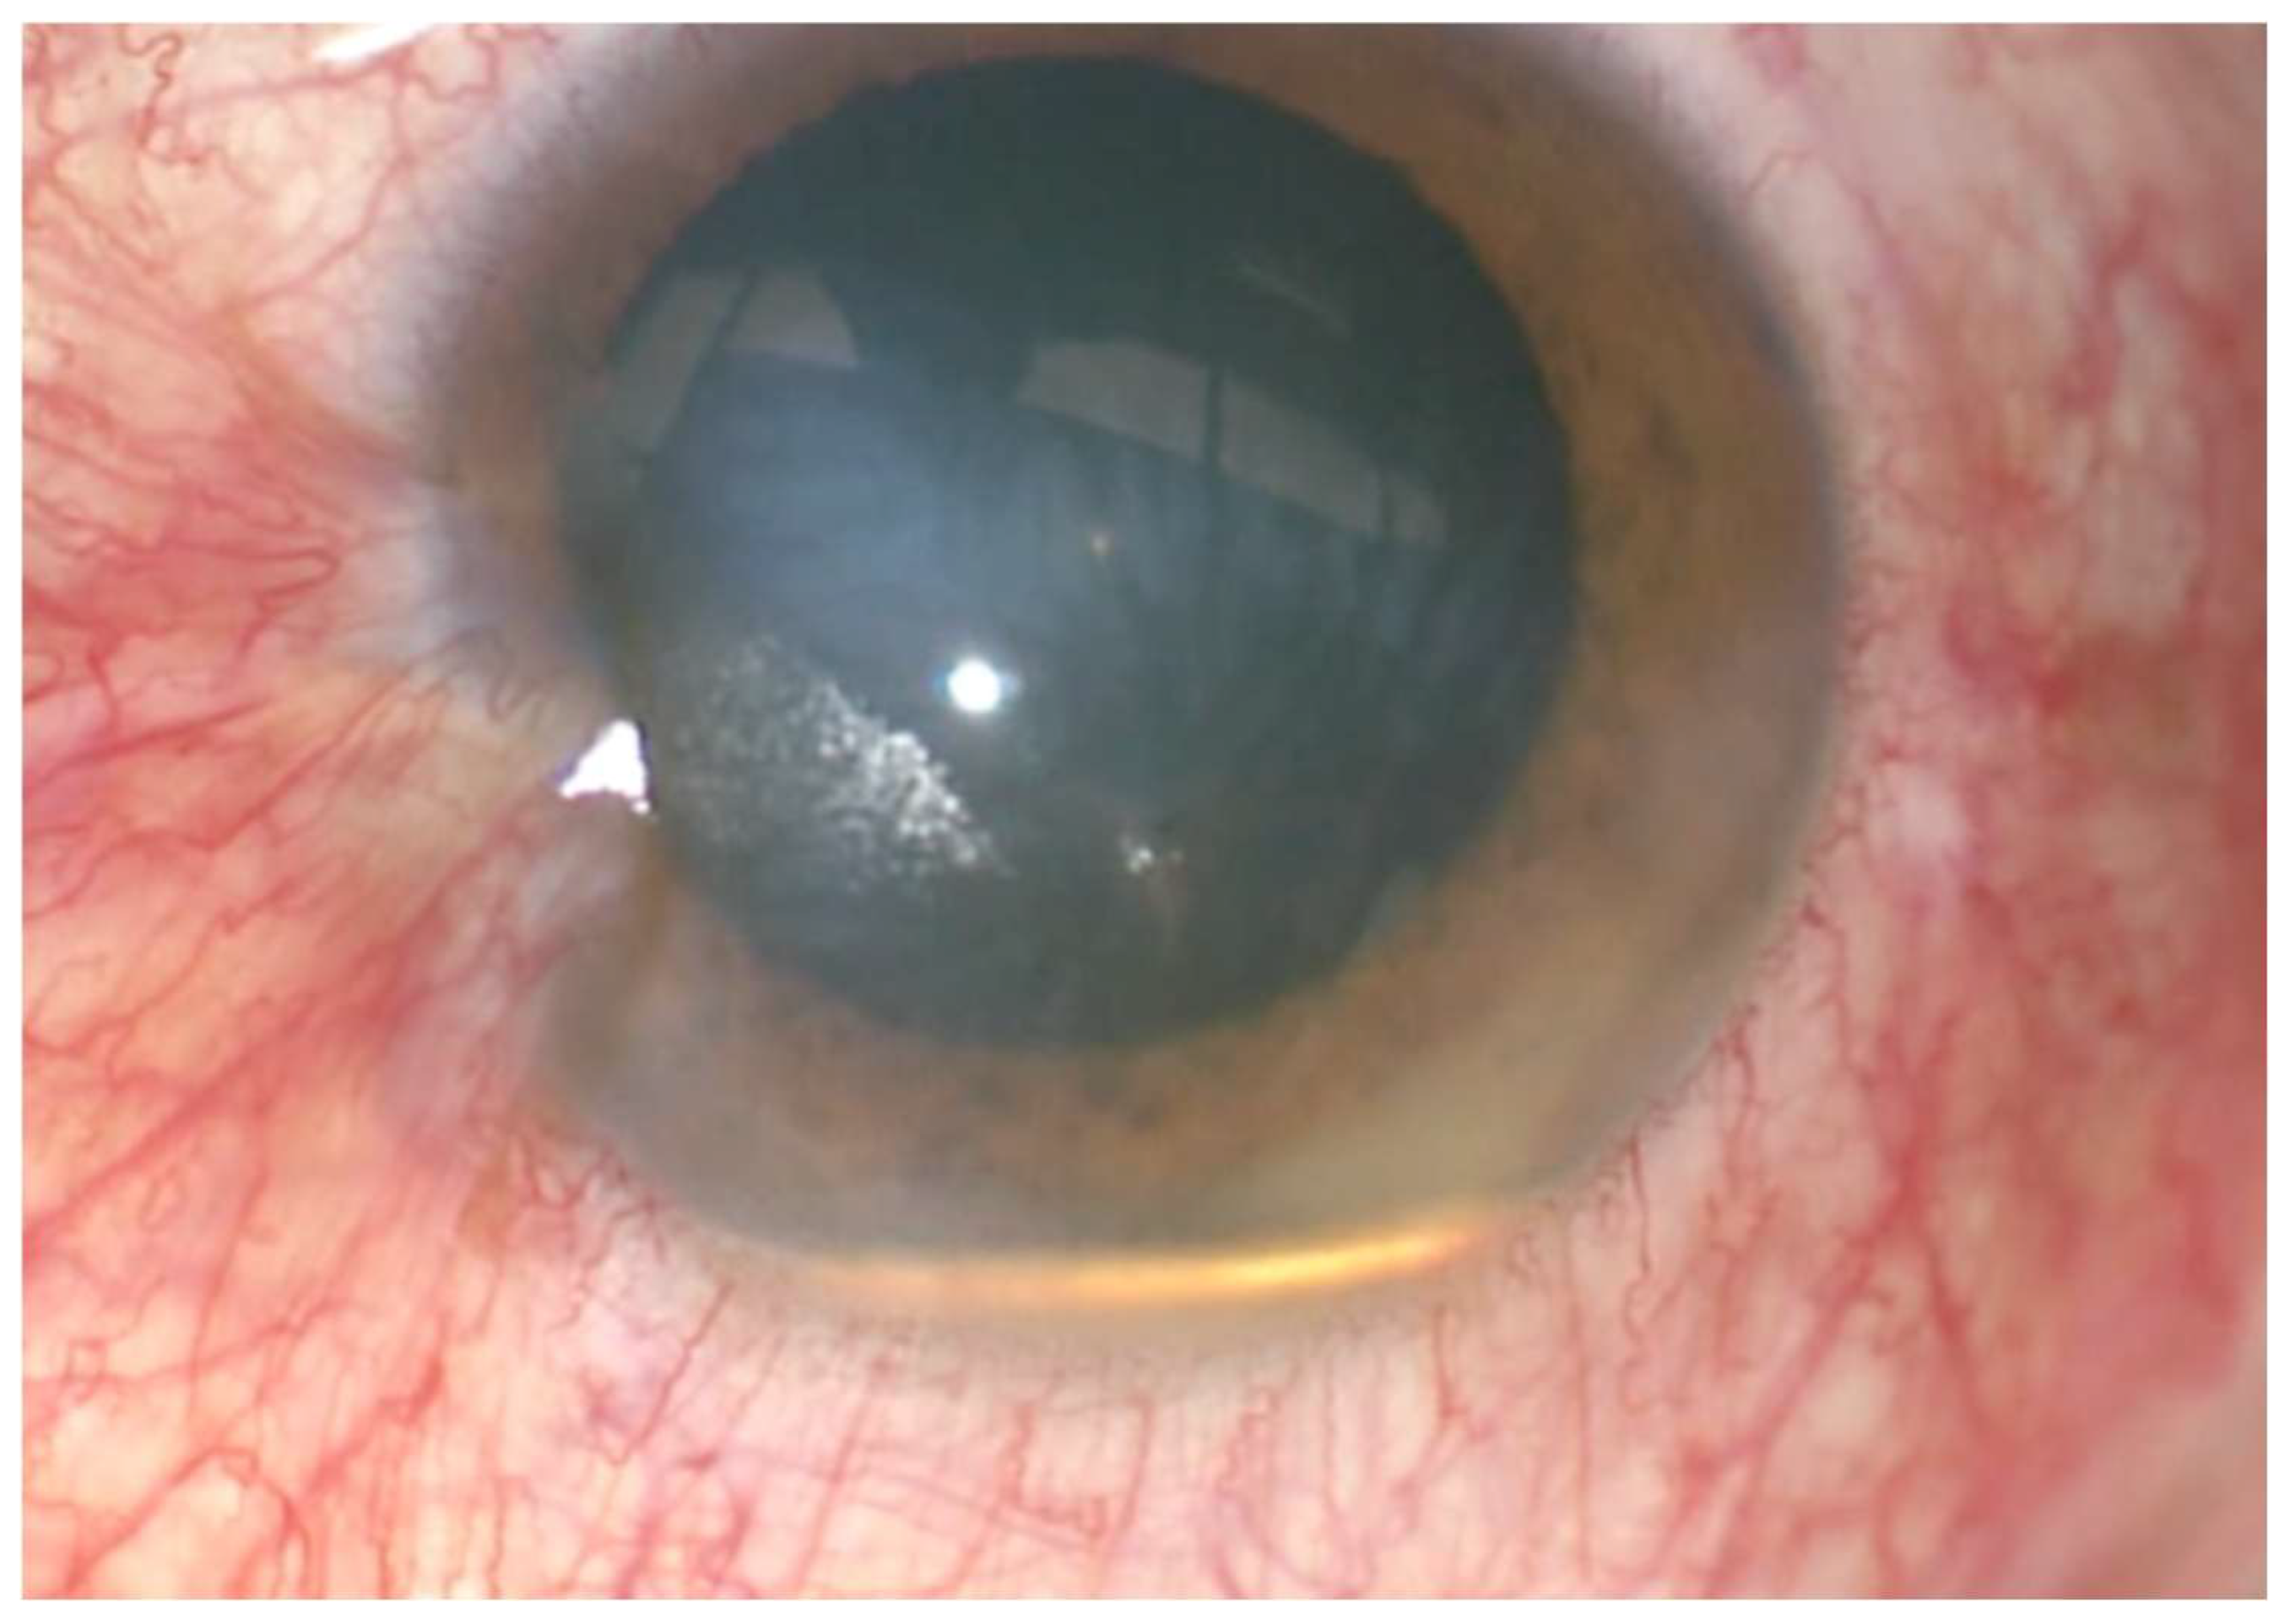

On the initial brief examination of the eye, the ocular appearance mimicked a golden-colored hypopyon. However, on slit-lamp examination, a metallic piece was appreciated with a small space between the piece and the bottom of the anterior chamber (Figure 1). Conjunctival hyperemia and a 2 mm self-sealed corneal laceration (with a negative Seidel sign) were also noted. He had no RAPD. CT orbits revealed a metallic intraocular foreign body resting in the anterior chamber of the left eye (Figure 2).

Figure 1.

Photograph of the anterior segment of the left eye.